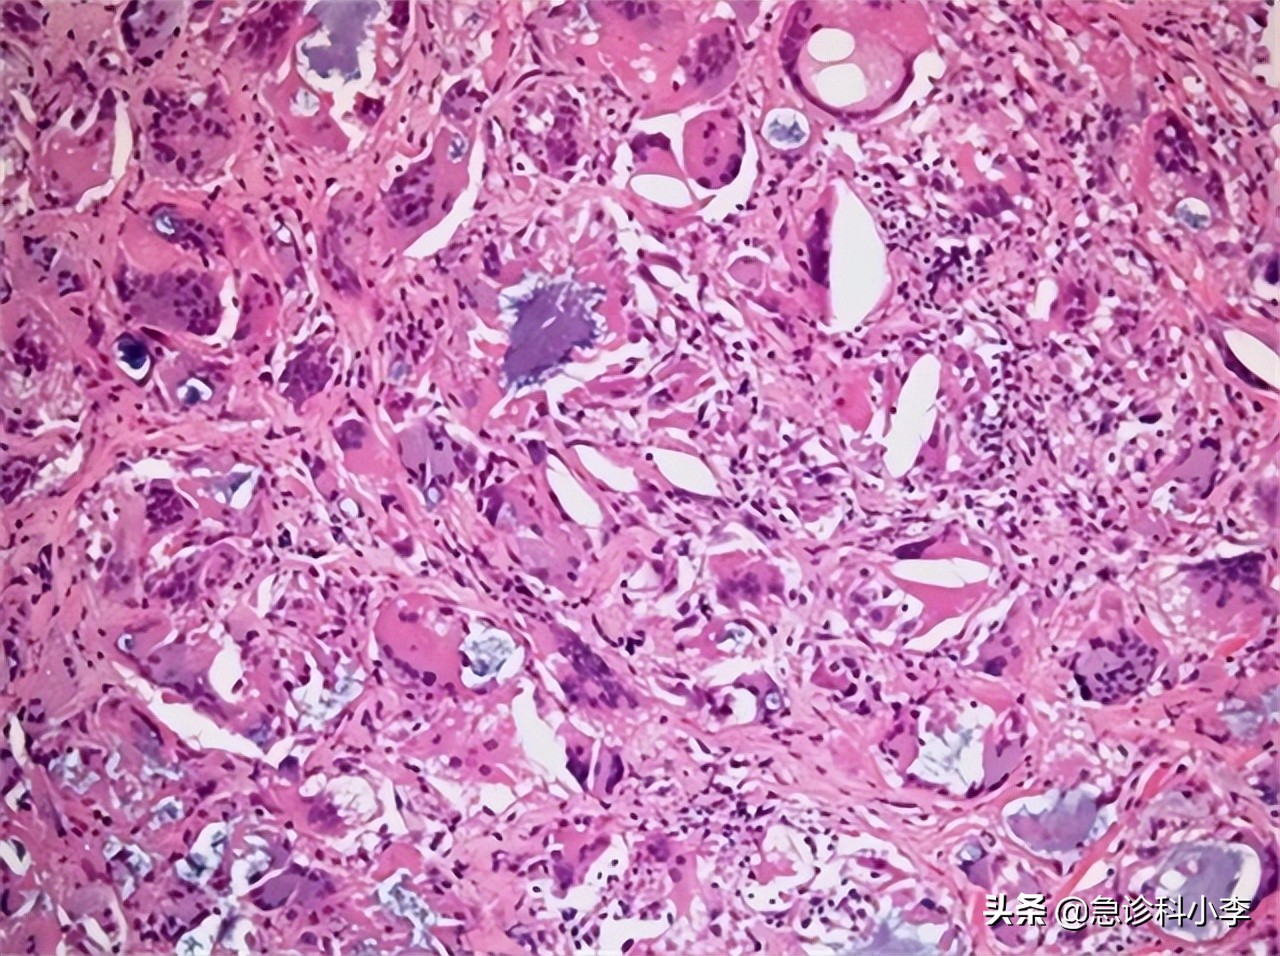

2、组织学检测

通过常规染色鉴定,可提供例如炎症程度、病变程度及病理分期等信息。